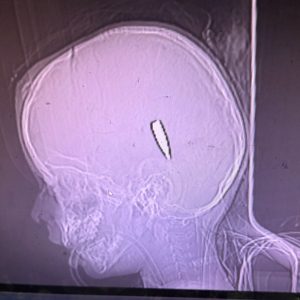

(গাজায় শিশুদের গলা এবং মাথায় shrapnel-এর টুকরো)